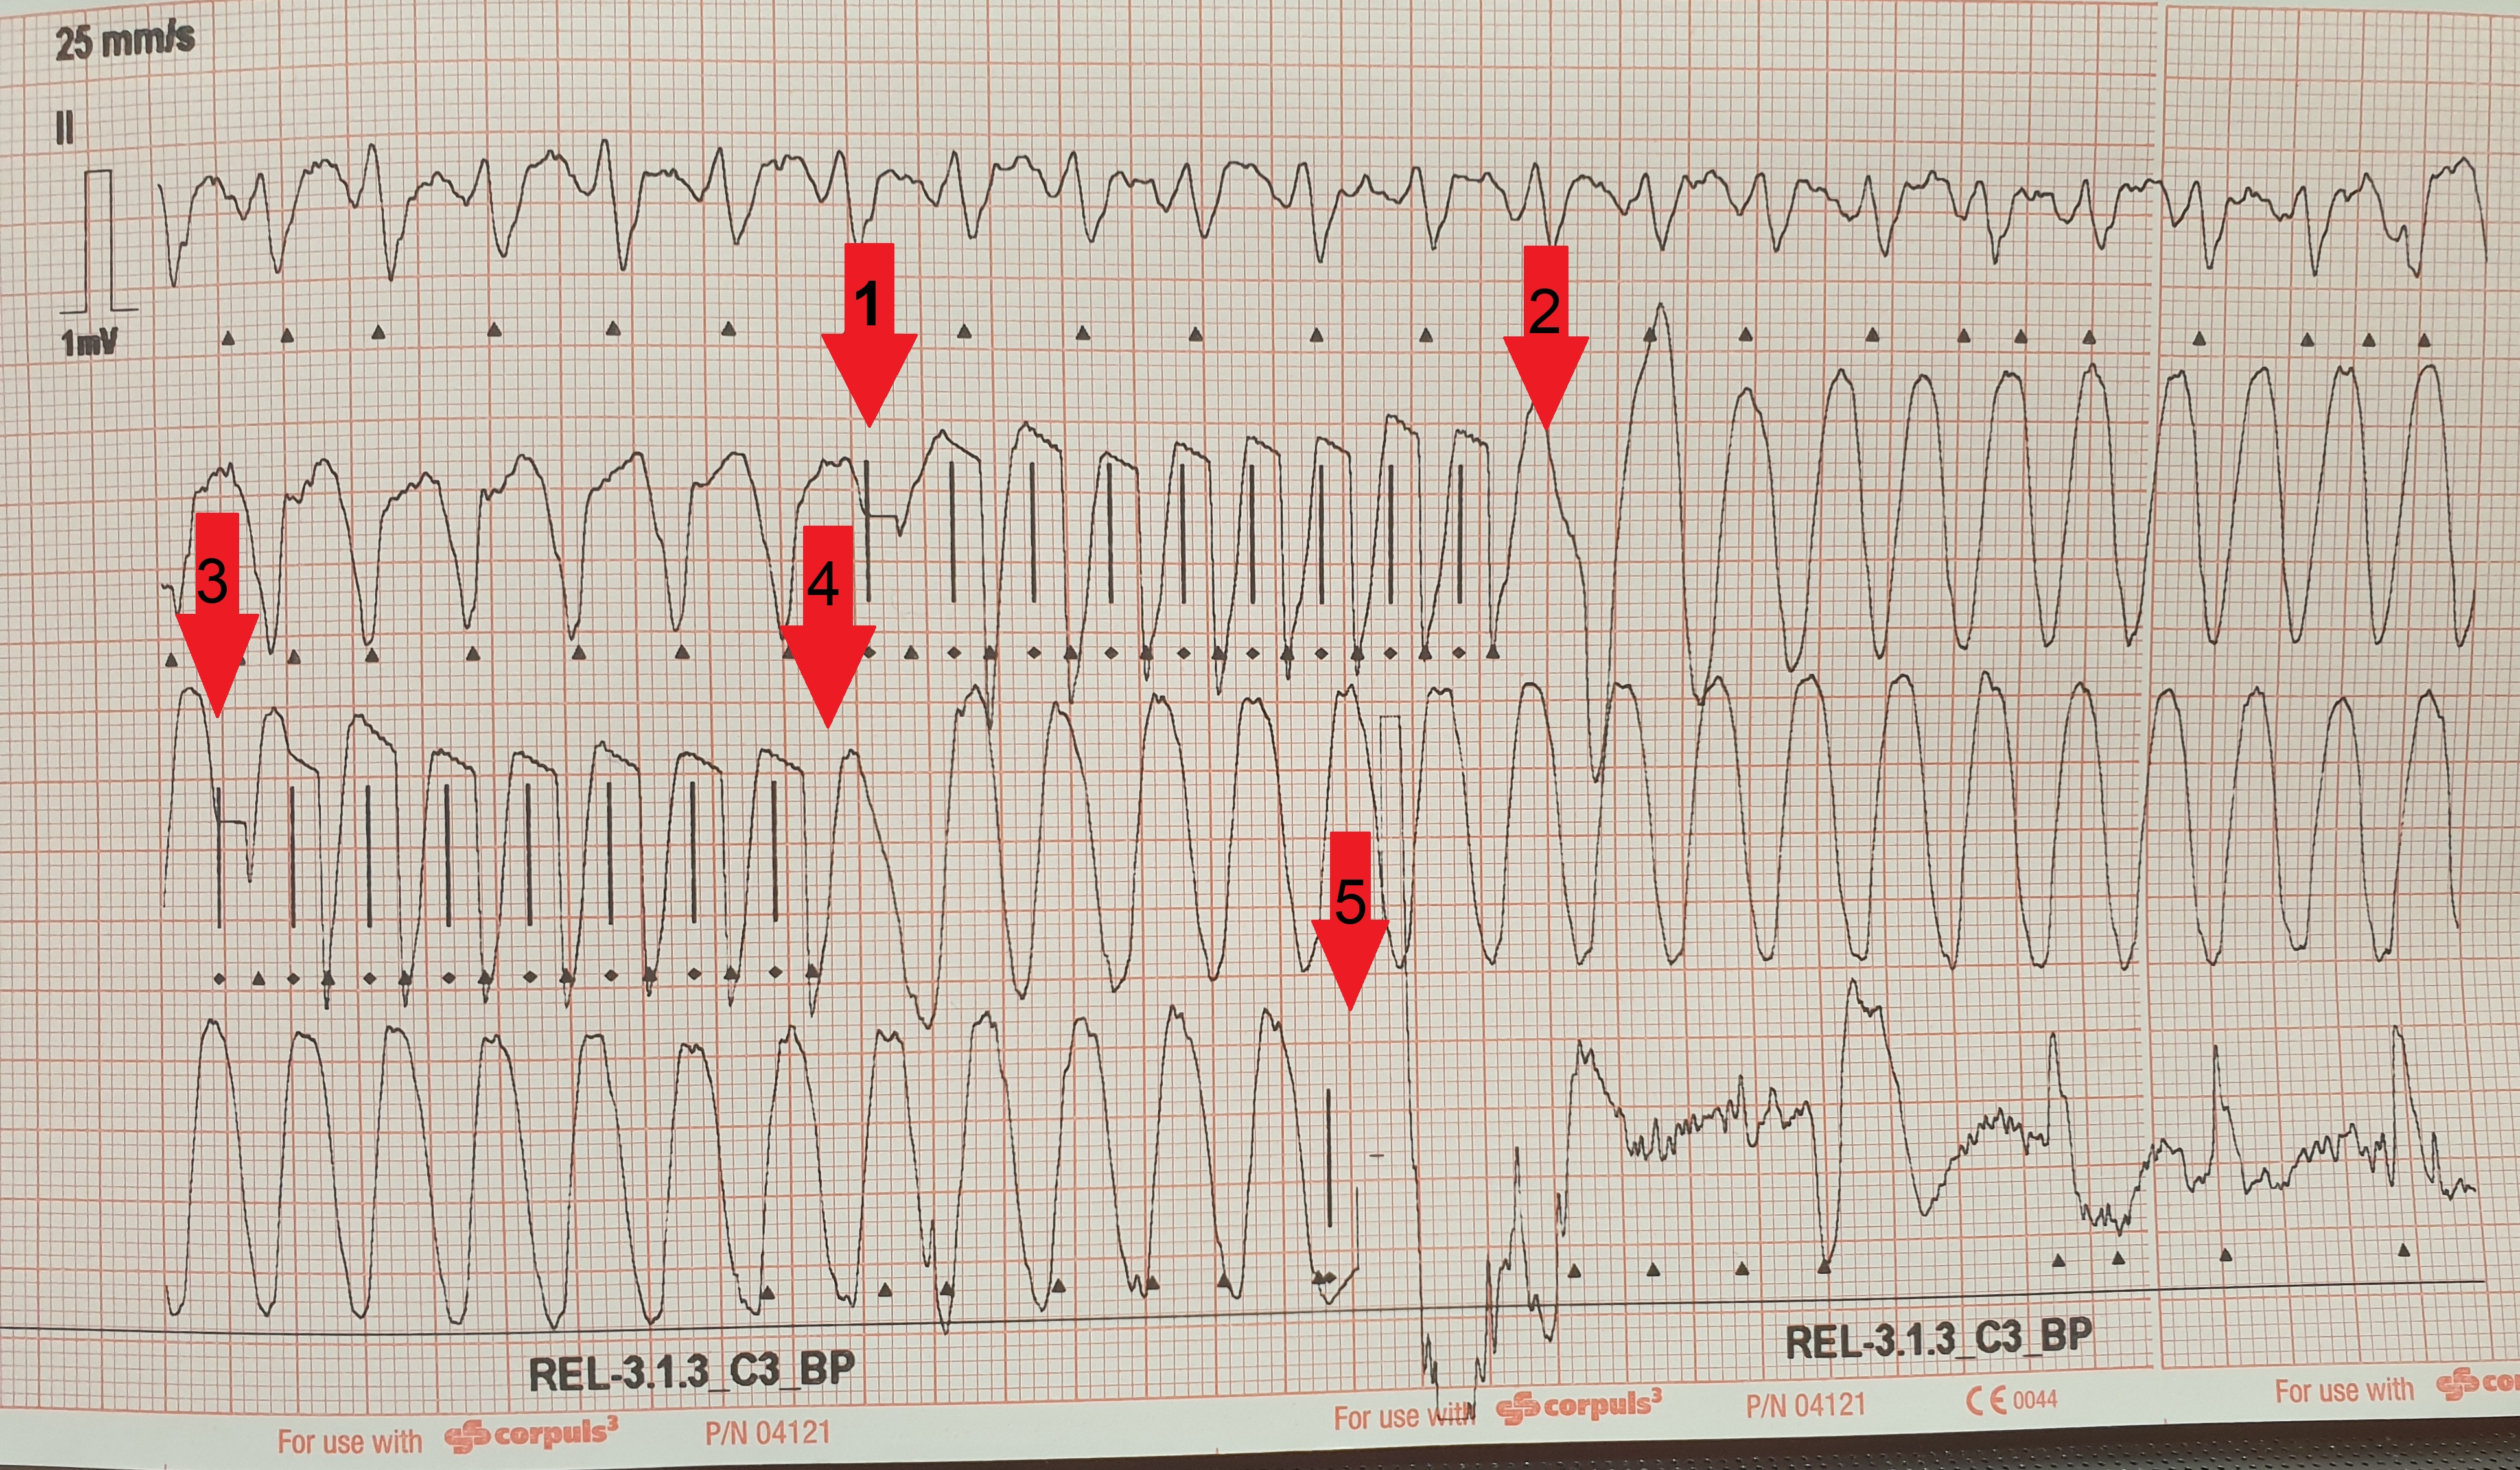

ekg-bild-2